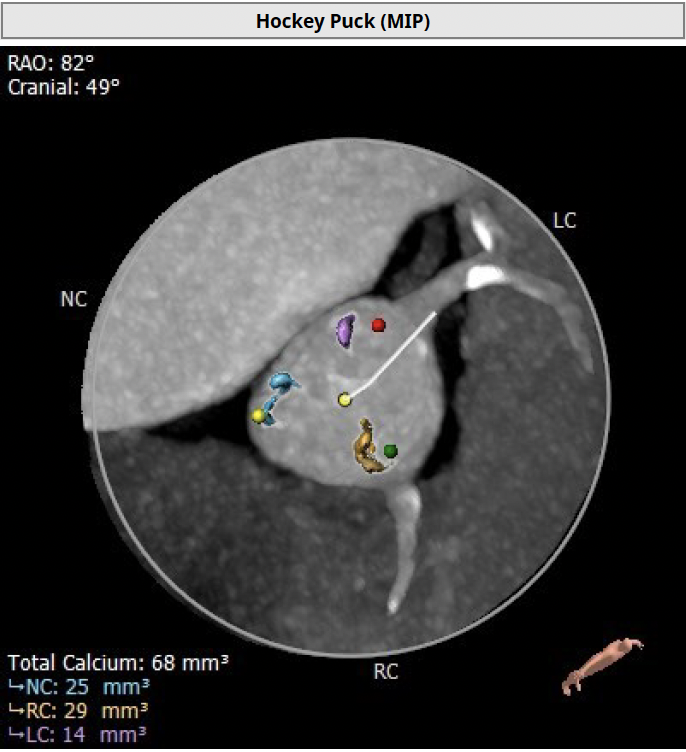

钙化积分68mm³

右冠